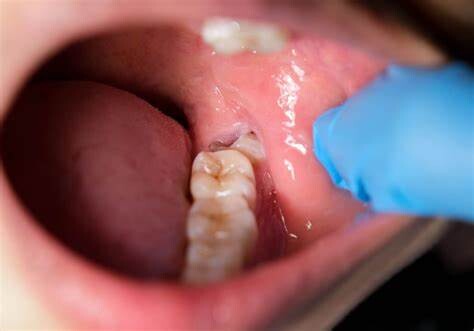

In some cases, jaw pain on one side can indicate underlying oral health problems. Some common issues that cause jaw pain are cavities, an abscessed tooth, gum disease, tooth decay, growth of wisdom teeth, missing or crooked teeth, and clenching or grinding your teeth.

Tooth Decay

The fully impacted or the partially impacted wisdom teeth are at greater risk of tooth decay, than other teeth. This usually happens, because of the location of the wisdom tooth, especially towards the back of the mouth, which is hard to clean. Moreover, since it lies at the back of the mouth, there are chances of food getting easily trapped between the gums and the tooth, promoting the growth of bacteria.